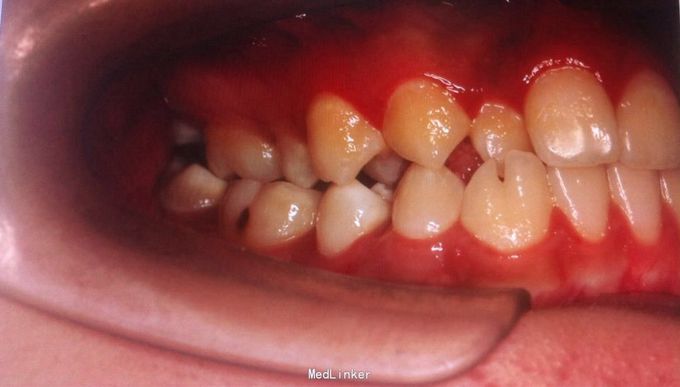

恒牙期 左右磨牙近中关系 12,22舌侧错位 32、33融合牙 右侧磨牙反合 上下牙列轻度拥挤 关节有弹响

安氏三类、后牙反合 不拔牙矫治,直丝弓矫治器,排齐整平上下牙列,解除后牙反合,矫治后覆合覆盖正常,磨牙中性关系,维持现有面型